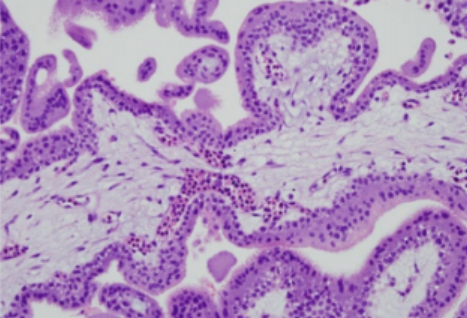

Según la apariencia de las glándulas endometriales en la foto, en que fase del ciclo menstrual esta y que hormona predomina:

Proliferativa y estrógeno (glándulas compactas, pequeñas y sin inflamación; reconstrucción del endometrio)